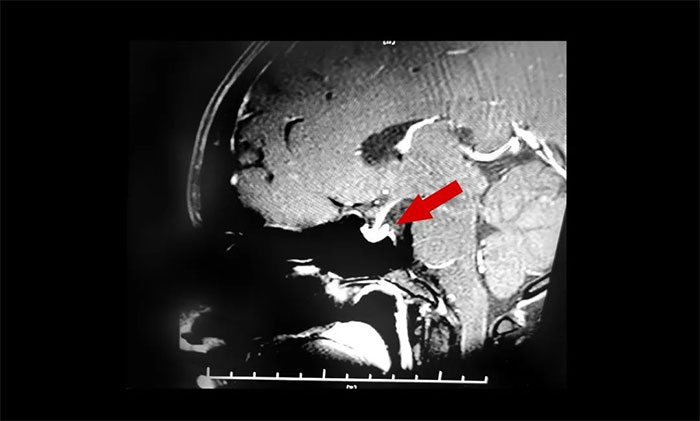

▲ 垂體腺瘤超蝶鞍生長

入院時查體,鞍區(qū)MRI平掃+增強顯示:蝶鞍稍擴大,鞍底骨質(zhì)下陷;垂體前葉右側(cè)見一矢橫高徑約1×1×1cm異常信號灶。檢查催乳素超3000μIU/mL,遠超正常值。

結(jié)合患者以往影像資料和內(nèi)分泌科檢查結(jié)果,李士其教授、潘仁龍主任會診后一致達成共識:泌乳素垂體瘤。